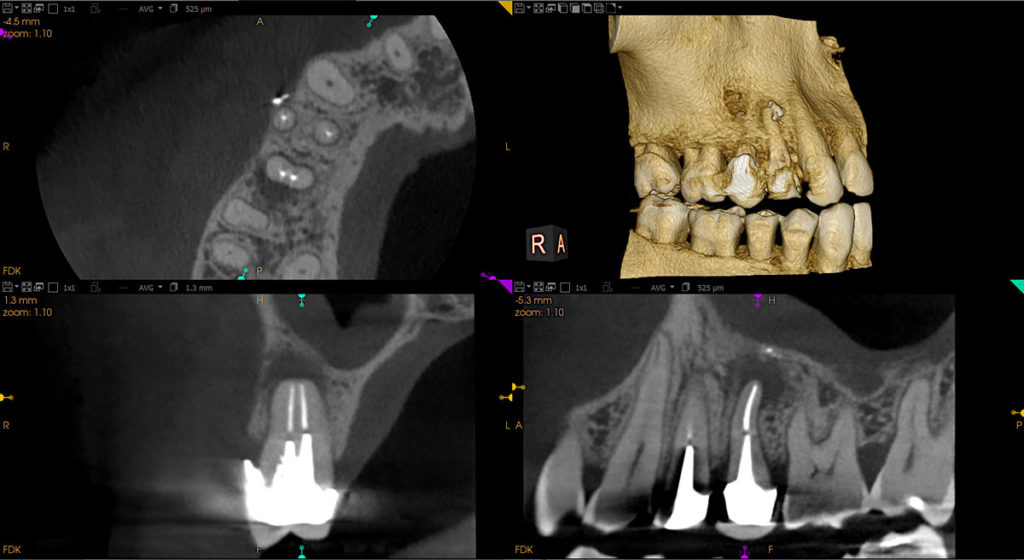

cs9600-5x5_endo-issues

Δημοσιεύθηκε 25 Σεπτεμβρίου 2018 στο 1200 × 656 σε cs9600-5x5_endo-issues